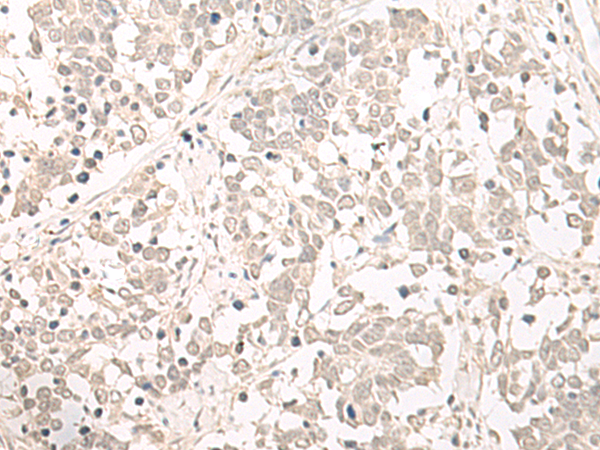

IHC positive control: |

Human cervical cancer and Human lung cancer |

IHC Recommend dilution: |

40-200 |